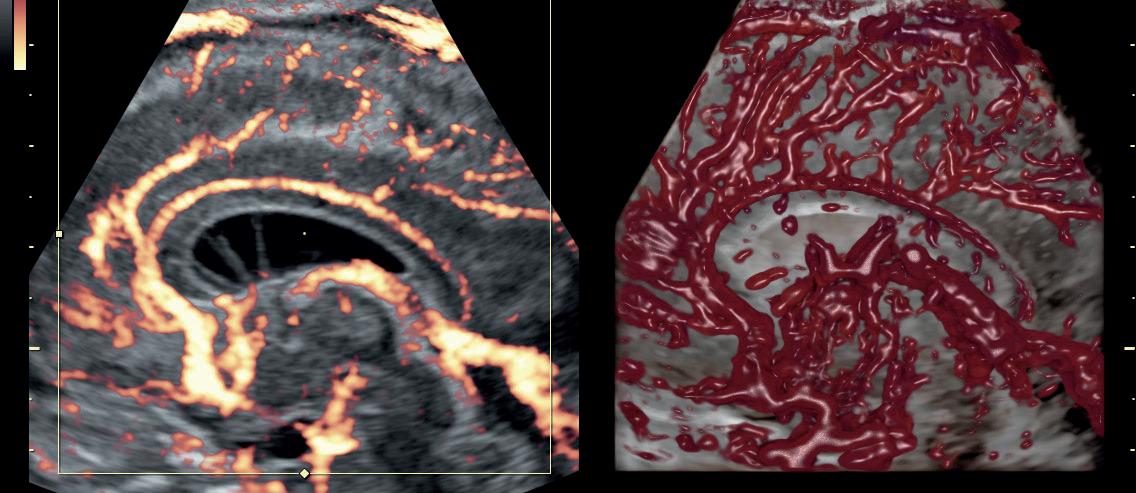

τμήματος Fetal Medicine, υπό την εποπτεία του καθηγητή Κύπρου Νικολαϊδη στο King’s College Hospital. Από το 2000 και για δύο χρόνια, προσέφερε τις υπηρεσίες της στο Αρεταίειο Νοσοκομείο Αθηνών, καθώς συμμετείχε στις δραστηριότητες του Τμήματος Υπερήχων και Εμβρυομητρικής Ιατρικής και στις δραστηριότητες της Β’ Μαιευτικής-Γυναικολογικής Κλινικής Πανεπιστημίου Αθηνών. Στο ίδιο νοσοκομείο και για τα έτη 2003-2006 εργάστηκε ως Επιστημονικός Συνεργάτης στο Τμήμα Υπερήχων και Εμβρυομητρικής Ιατρικής της Β’ Μαιευτικής και Γυναικολογικής Κλινικής του Πανεπιστημίου Αθηνών. Από το 2023 είναι Clinical Instructor του Nicosia University.